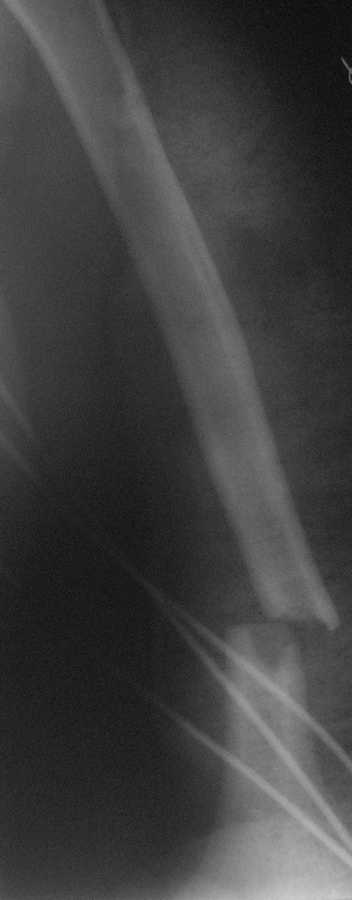

Перелом нестабильный, тактика - если позволяет сосояние больной, оперативное лечение. Как пример см. ниже, можно без скобы - стяжки с ЭПФ.

Уважаемый товарисч.Данный перелом можно вылечить антероградным, ретроградным штифтованием, пластиной, аппаратом внешней фиксации, вытяжением за локтевой отросток на шине ЦИТО. Учитывая наличие тяжелой ЧМТ предпочтение должно отдаваться минимальноинвазивной технике.

Качество паредставленных Вами рентгеновских снимков крайне низкое, что косвенно свидетельствует об общей культуре работы в Вашем отделении.